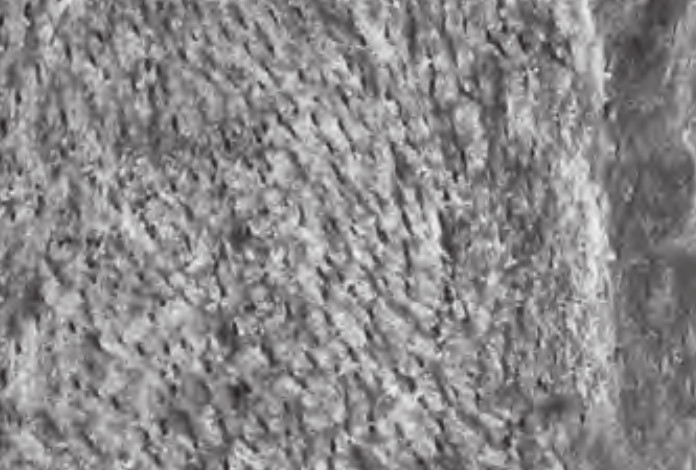

Ti-oss wykorzystuje 100% kości gąbczastej. Większość ksenograftów wykorzystuje mieszankę kości korowej i gąbczastej. Wszystkie ksenografty muszą zostać przetworzone przed użyciem u ludzi w wysokiej temperaturze, tworząc twardsze, gęstsze struktury z mniejszą liczbą mikroporów, które nie są preferowane przez nowe komórki kostne. Ti-oss stosuje wyrafinowaną obróbkę przy użyciu niskich temperatur uzupełnionych o środki chemiczne kontrolujące pH, które zachowują optymalną porowatość i strukturę porów, zapewniając doskonałą zwilżalność, powierzchnię i angiogenezę – prekursor szybkiej waskularyzacji i wczesnego gojenia.

Proces tworzenia nowej tkanki kostnej inicjowany jest poprzez przyleganie skrzepów krwi, co nazywane jest również tworzeniem sieci fibrynowej. Do tego procesu niezbędna jest szorstka i hydrofilowa powierzchnia; bez niej nie można oczekiwać skutecznego wzrostu tkanki kostnej, podobnie jak trudno jest uzyskać tarcie na gładkiej, szklistej powierzchni.

Nasze doświadczenie w produkcji w średnich temperaturach oraz badania prowadzone we współpracy z wiodącymi instytucjami naukowymi pozwalają nam tworzyć materiał przeszczepowy o powierzchni wiernie przypominającej ludzkie kości.